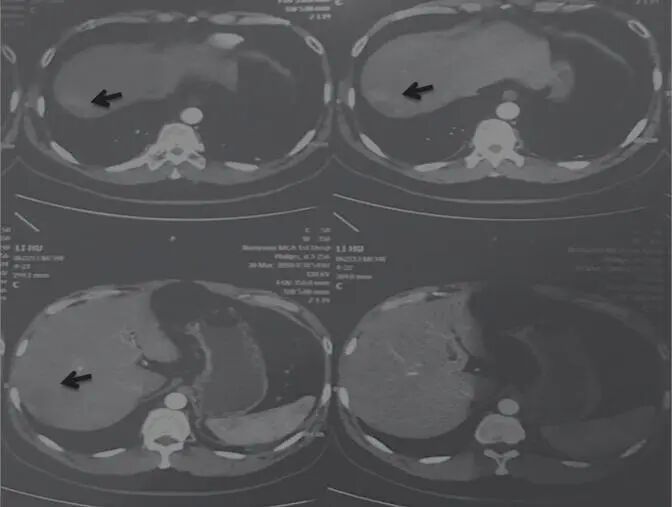

2017年11月1日,AFP 1027ng/mL查說(shuō)明腫瘤并沒有消失,但是病變部位有所減?。▓D2)。

圖2 舒達(dá)少陽(yáng)防治腫瘤驗(yàn)案2017年11月1日CT結(jié)果